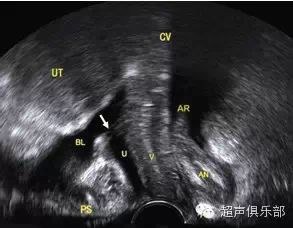

近年来,超声以其无创、可重复性和费用低廉等优点被广泛应用于临床,但用于对FPFD的诊断尚属起步阶段。超声成像技术对盆底的评估主要包括盆底解剖形态和盆底器官活动度的评估。盆底超声的先驱,澳大利亚的HP Dietz教授通过双盲法研究发现了临床POP-Q系统和超声量化盆腔器官脱垂具有很好的相关性。常规二维超声在静息、最大Valsalva动作和缩肛动作时观察盆底结构变化的情况,主要观察前腔室、中腔室和后腔室,见图1。常规经会阴二维超声因受骨性盆腔结构的影响,难以对盆底软组织进行成像,且仅局限于正中矢状切面的成像。盆底三维超声因其多平面成像的优势,可以获得盆底的轴平面,能更直观、多切面观察盆底重要支持结构---肛提肌(见图2)。TUI模式及实时动态成像为肛提肌的解剖结构、形态特点及功能的检测提供了新的方法。

图1. 盆底二维超声:盆底正中矢状切面,由腹侧至背侧依次显示耻骨联合(PS)、尿道(U)、膀胱颈(箭头所示)、膀胱(BL)、阴道(V)、宫颈(CV)、直肠壶腹部(AR)、肛管(AN)和会阴体(P)。